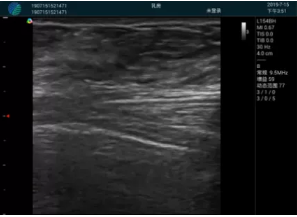

頸動(dòng)脈血流充盈飽滿,無外溢